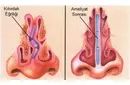

Kıkırdak Doku Çeşitleri Kıkırdak doku, bağ dokuları arasında yer alan, esnek ve dayanıklı bir yapıya sahip olan dokulardır. Farklı türleri ve işlevleri, vücudun çeşitli bölgelerinde önemli roller üstlenmektedir. Bu makalede, kıkırdak dokunun çeşitleri ve özellikleri detaylı bir şekilde ele alınacaktır. Kıkırdak Doku Türleri Kıkırdak doku üç ana türde sınıflandırılmaktadır: hyalin kıkırdak, elastik kıkırdak ve fibröz kıkırdak. Her bir tür, farklı yapısal özelliklere ve işlevsel amaçlara sahiptir.

Kıkırdak Dokunun Özellikleri Kıkırdak dokunun bazı ayırt edici özellikleri şunlardır: